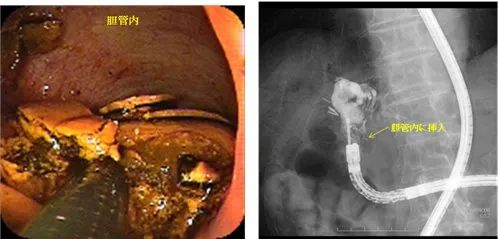

ダブルバルーンERCP(DB-ERCP)【下図】

胃全摘後のRoux-en Y再建症例に対するダブルバルーン内視鏡を用いた内視鏡的総胆管結石治療。 胆管内に内視鏡を直接挿入し、結石を破砕している。 - 内視鏡的胆管ステント留置術(EBS)